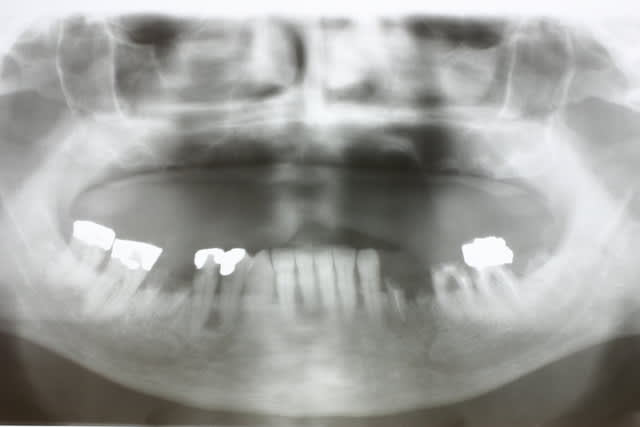

mais comment tu fais pour bosser avec des pano aussi dégueulasses ?

tu devrais investir, je ne doute pas que tu saches interpréter des panos mais quand même, c'est du confort pour bosser. pourquoi s'en priver?

Pfs les patients arrivent avec leur pano de chez leur praticien

Il y en une bien floue ds la bande mais bon comme 1er doc avant les scanners ça peut déjà donner une idée